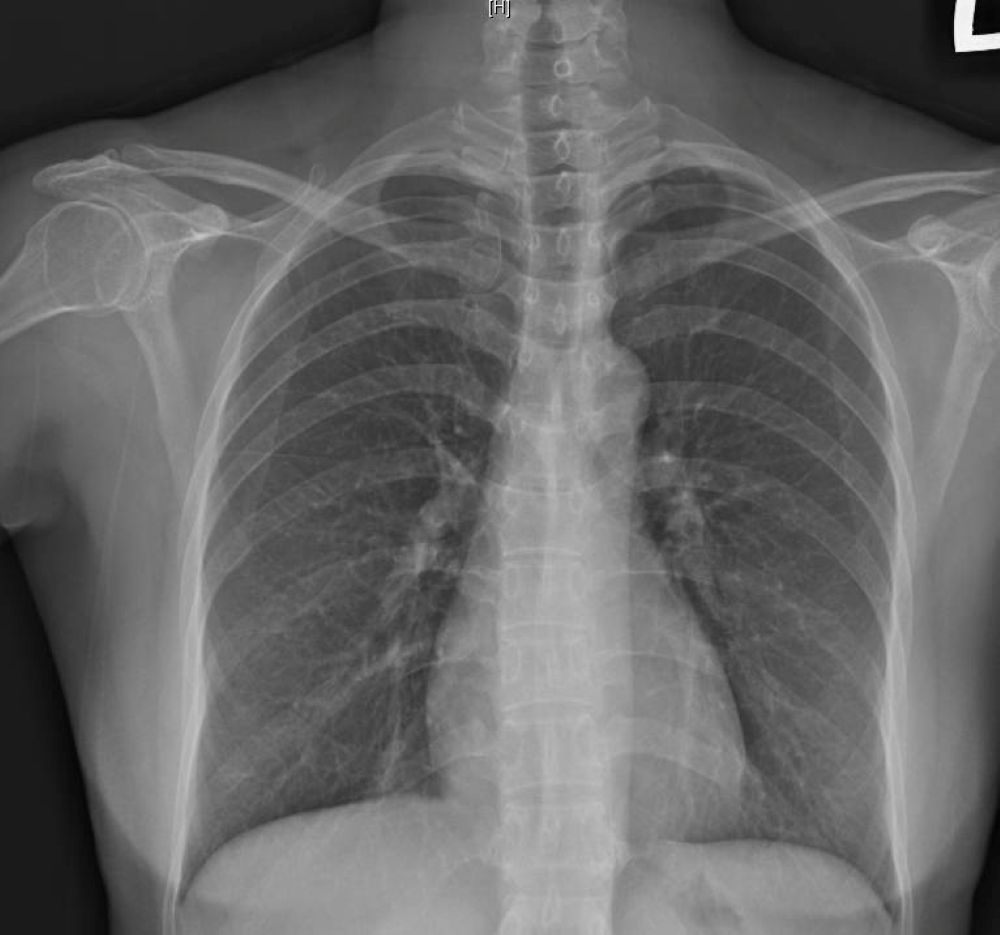

蕭惠元表示,每當季節交替或日夜溫差大的時期,一些流感或風寒感冒的患者,在發燒、流鼻水等症狀康復後,會有持續一段時間的乾咳,甚至持續超過3週的咳嗽,似乎難以斷根,經X光與肺活量檢查,顯示無明顯浸潤或肺炎陰影,排除肺炎、肺癌或肺結核等重大疾病後,可確診為「感染後咳嗽」,經過止咳藥物治療1週左右,即可痊癒。